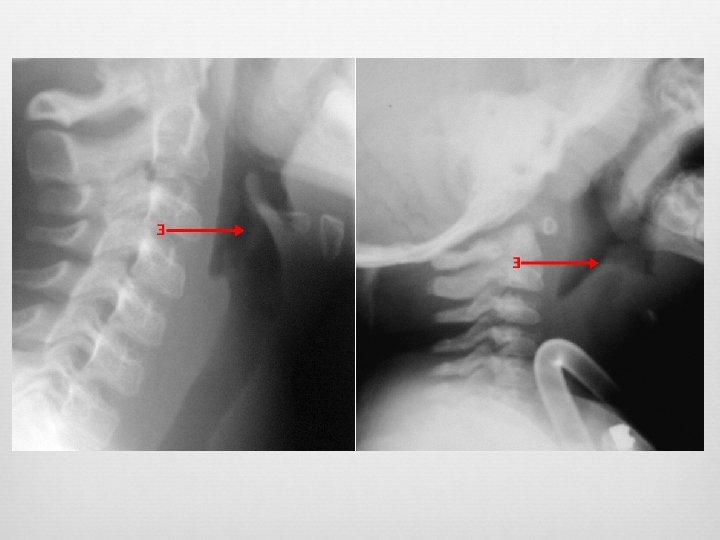

Retropharyngeal Infection Widened retropharyngeal space C 2 – 7 mm or C 6 – 14 mm (kids) C 6 – 22 mm (adults) Reversal of normal cervical lordosis Foreign body Air-fluid level Gas

False Pre-vertebral Swelling Oblique lateral Neck flexion Crying